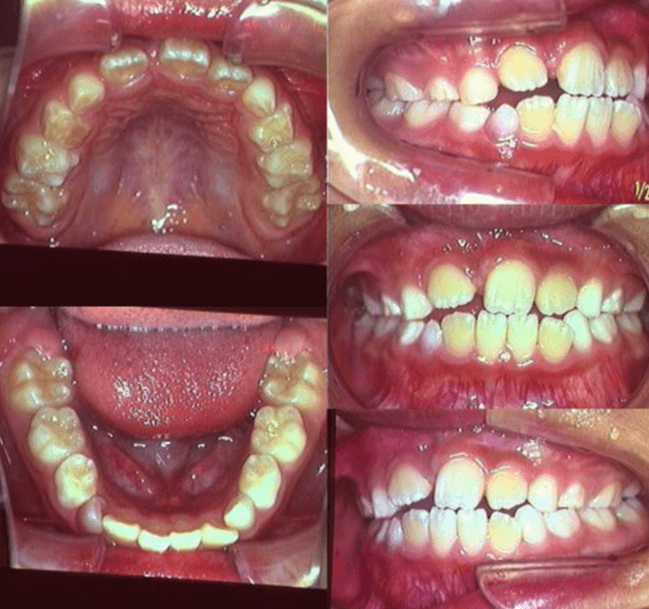

| 年齢・性別 | 8歳9ヶ月の女児 |

|---|---|

| 主訴 | 歯並びの乱れを気にされて来院された患者様です。将来的なスペース不足と歯のねじれ(翼状捻転)が懸念されました。 |

| 治療期間・回数 | 2年10ヶ月・19回 |

| 費用 | 430,000円(税別) |